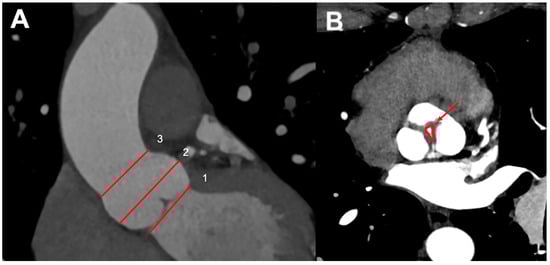

4. Assessment of Chronic Aortic Regurgitation in BAV: Usefulness and Limitations of Cardiac-CT

4.1. Aortic Root and Valve Evaluation

- Alkadhi, H.; Desbiolles, L.; Husmann, L.; Plass, A.; Leschka, S.; Scheffel, H.; Vachenauer, R.; Schepis, T.; Gaemperli, O.; Flohr, T.G.; et al. Aortic regurgitation: Assessment with 64-section CT. Radiology 2007, 245, 111–121. [Google Scholar] [CrossRef] [PubMed][Green Version]

- Jassal, D.S.; Shapiro, M.D.; Neilan, T.G.; Chaithiraphan, V.; Ferencik, M.; Teague, S.D.; Brady, T.J.; Isselbacher, E.M.; Cury, R.C. 64-slice multidetector computed tomography (MDCT) for detection of aortic regurgitation and quantification of severity. Investig. Radiol. 2007, 42, 507–512. [Google Scholar] [CrossRef]